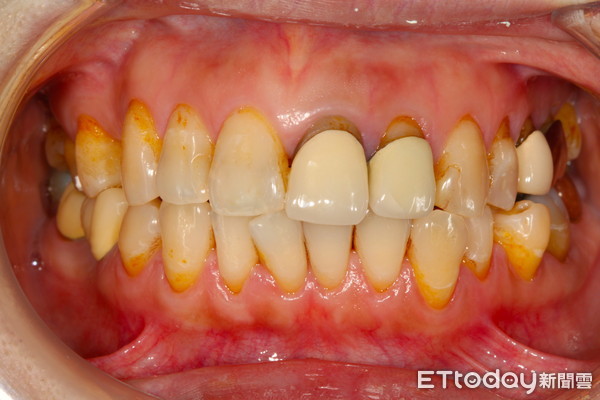

▲長期飲用茶、咖啡或含有色素之飲品易使牙色發黃暗沈,產生不美觀的黃板牙。(圖/中壢天晟醫院提供)

另外,徐偉軒醫師也提醒,多數市售飲品或手搖飲料會添加食用色素,如黑糖珍珠可能添加焦糖色素,有些人天天一杯飲料或咖啡,工作、打電腦又含著一口茶飲,牙齒長時間浸潤會使色素沈著,牙色可能會發黃暗沈,容易產生不美觀的黃板牙。